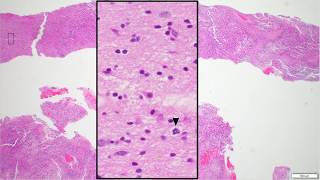

Glioblastoma histopathologic diagnosis Adventures in Neuropathology video

Glioblastoma histopathologic diagnosis - Adventures in Neuropathology

Glioblastoma histopathologic diagnosis - Adventures in Neuropathology Glioblastoma IDH Wildtype Histopathological Diagnosis